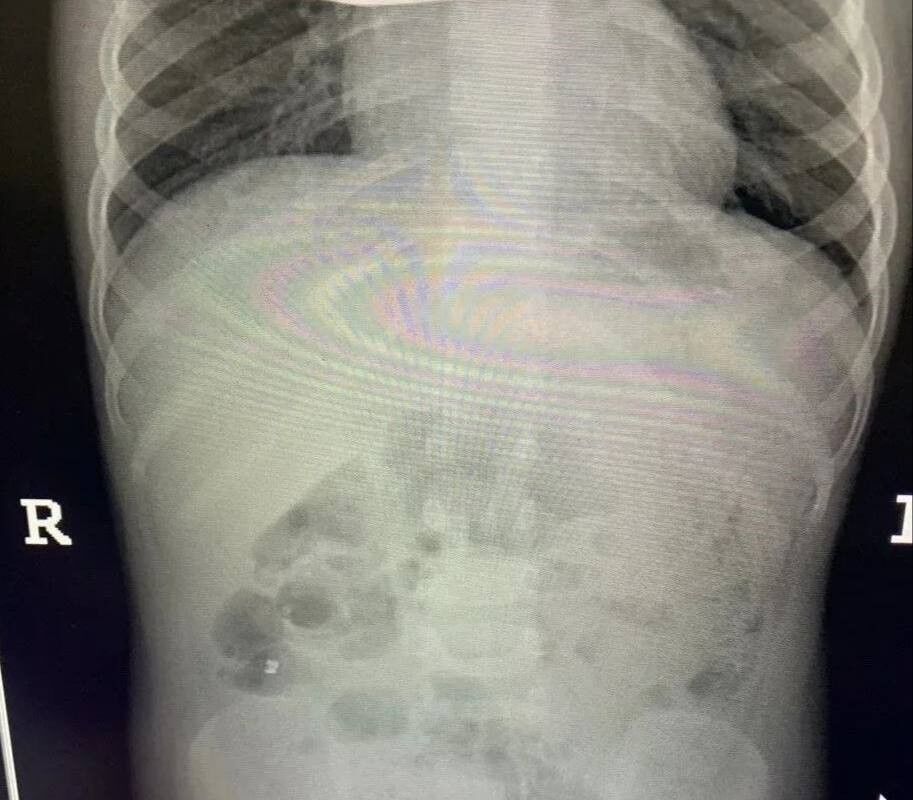

Инцидент произошел в Балашихе — малолетнюю пациентку с жалобами на острую боль в животе доставила в больницу бригада скорой помощи. Обследование показало, что внутри у ребенка большое количество металлических инородных тел. Девочку немедленно отправили на операционный стол.

Врачи приняли решение обойтись без полостного вмешательства. Через крошечные проколы специалисты аккуратно извлекли 20 магнитов из организма ребенка — они успели притянуться друг к другу и прожечь стенку кишки насквозь. Пять штук и вовсе мигрировали в область малого таза.